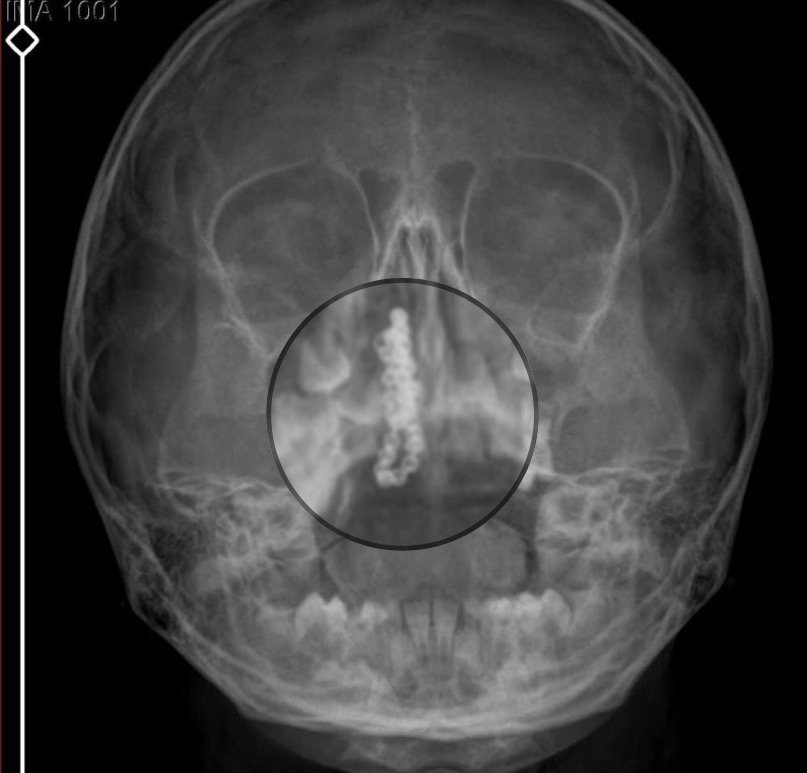

Kentte yaşayan Gökhan-Nalan Tekin çifti, yaklaşık 4 ay önce şiddetli burun kanamasının yanı sıra akıntı şikayetleriyle kızları Polen’i, bir özel hastaneye götürdü. Burada röntgeni çekilip, tetkikleri tamamlanan küçük kıza, iddiaya göre enfeksiyon teşhisi konulup, ilaç verildi. Eve dönen aile, kanama ve akıntının geçmemesi üzerine bu kez Rize Devlet Hastanesi’ne giderek Kulak Burun Boğaz Polikliniği’ne başvurdu. Devlet hastanesindeki doktorun incelemesi ve kapsamlı röntgen çekilmesi sonrası Polen’in burnunda metal cisim olduğu fark edildi. 2 yıldır burunda kaldığı değerlendirilip, küçük top şeklinde tırnak makası zinciri olduğu belirlenen cisim, başarılı ameliyatla çıkarıldı. Bir süre tedavisi sürdürülen Polen, sağlığına kavuşunca taburcu edildi. Özel hastane yetkilileri, konuyla ilgili açıklama yapmazken; aile suç duyurusunda bulunacaklarını söyledi.

Kızının burnundan sürekli siyah renkte akıntı olduğunu anlatan Gökhan Tekin, “Çocuğumun burnundan kanama ile sürekli siyah akıntı geliyordu. Özel hastaneye götürdüm. Özel hastanede film çekildi, hiçbir bulguya rastlanılmadığı söylendi. O siyah leke de enfeksiyona dayalı olan bir şey olduğu bize söylendi. Eve geldik, akıntı sürmesi üzerine bu kez devlet hastanesine başvurduk. Burunda metal zinciri fark ettiler. Böyle bir ihmalkarlık olabilir mi? Özel hastaneye gidiyoruz, paramızla rezil oluyoruz. Zincir, 2 yıldır burnunda ve devletimizin hastanesinde iyi bir doktorumuz zinciri ortaya çıkarıyor, kızım ölümden dönüyor. Ben sonuna kadar bu işin peşini bırakmayacağım. Sonuna kadar hukuk mücadelesi vereceğim. Bu da diğer hastalarımıza ibret olsun. İşte, bakın koca bir zincir. ‘Bulguya rastlanılmadı’ deniliyor” dedi.

Kızının ameliyat sonrası durumunun iyi olduğunu söyleyen Tekin, “İnanır mısınız bize ‘Evde soba mı yanıyor? Acaba kömür isten dolayı mıdır bu?’ dendi. Böyle bir şey olabilir mi? Ameliyattan çıkan parmağım kadar zincir. Devlet hastanesindeki doktor da ‘Bu nasıl gözden kaçılabilir? Böyle bir pozisyon nasıl görülmeyebilir?’ yorumunda bulundu. Allah’a şükür olsun atlattık. Şu anda durumu, vaziyeti iyidir. Ben şuna inanıyorum doktor da bir şans işidir. Bakın paramızla özele gideriz ya hani bizde, daha iyi ilgilenirler. Oysa devlet hastanesindeki doktorumuz olayı meydana çıkardı” diye konuştu. (DHA)